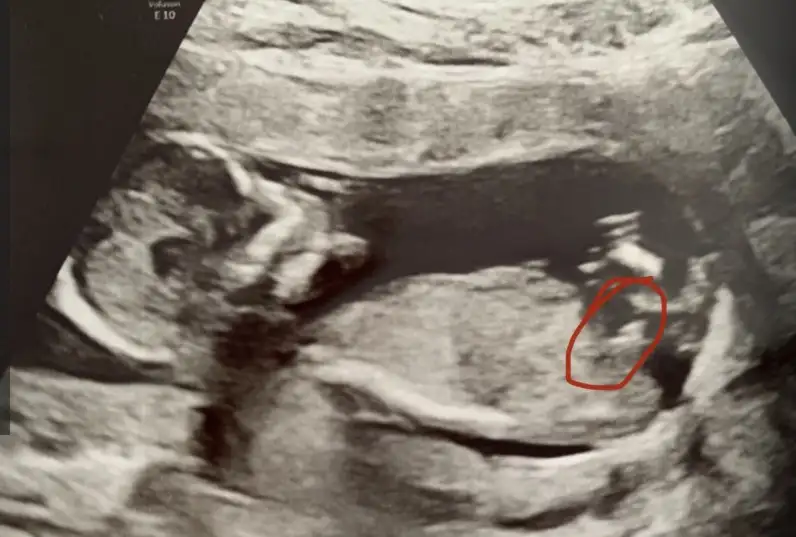

Kizlar merhaba biz doktordan geliyoruz hersey yolunda. Ben Isviçre deyim burda 16. haftadan once soylemiyolar cinsiyeti. Nub teorisine gore fikirlerinizi alabilirmiyim doktoru biraz zorladim erkek gibi dedi ama emin degilim dedi

Şu gördüğüm şey nub ise bence de erkek canım.